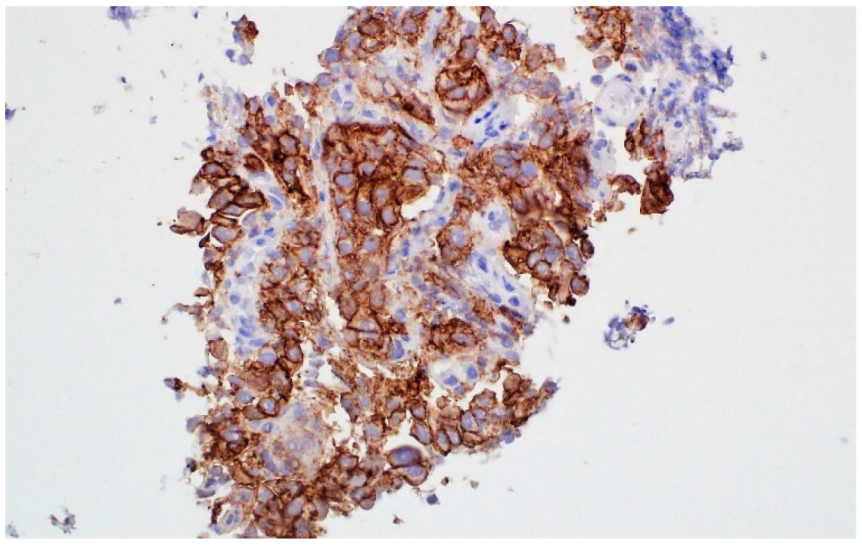

2. Case 1

3. Case 2